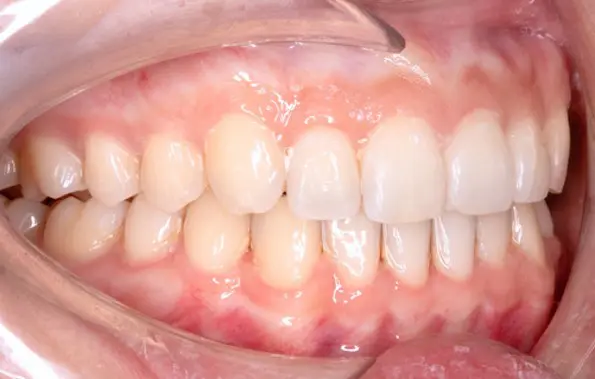

After